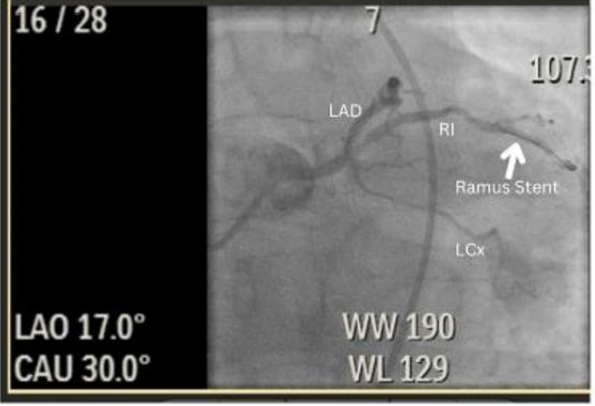

He successfully underwent a percutaneous transluminal coronary angioplasty (PTCA) with two DES placements in the mid-LAD and the mid ramus intermedius (Figure 2 and Figure 3) with post-procedure initiation of 90mg Ticagrelor and Aspirin along with guideline-directed medical therapy.

Figure 3: Left anterior oblique caudal view. This angiographic image shows the stented mid- ramus intermedius (white arrow).